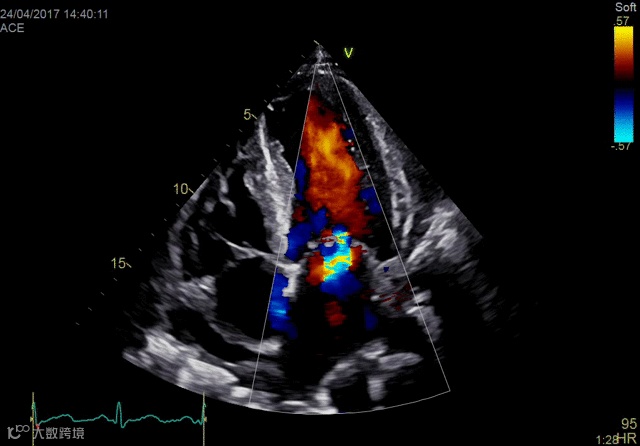

较慢的帧率和3-D超声的较大费用限制了其广泛采用,但其在一些专业领域的应用有助于快速扩展治疗,如经导管结构性心脏介入。当专家使用成像进行程序规划或指导时,3-D的使用具有很大的应用,其中3-D可以提供解剖学的“外科医生视野”。该技术还用于帮助指导复杂解剖结构中的导管手术。

Vivid E95心脏成像系统

2018年,GE医疗集团发布了其cSound图像重建技术的Imaging Elevated版本。该技术有助于Vivid E95心脏成像系统的成像质量,工作流程和量化。它利用GPU处理来提高音量帧速率,GE称为音量最大值或Vmax。与上一代系统相比,这使得TEE的帧速率几乎可以达到三倍。

佳能Aplio 900 CV系统还在2018年推出了一种新方法,通过称为四腔室跟踪的回声可视化心脏。它在一个三维视图中跟踪所有四个腔室的血容量。它提供腔室的舒张末期和收缩末期视图。这允许一次完成整个心脏功能的图像,而不是一次查看一个腔室。